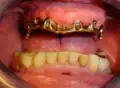

Prothese über der Stegkonstruktion eingesetzt -

Frontansicht des Zahnersatzes -